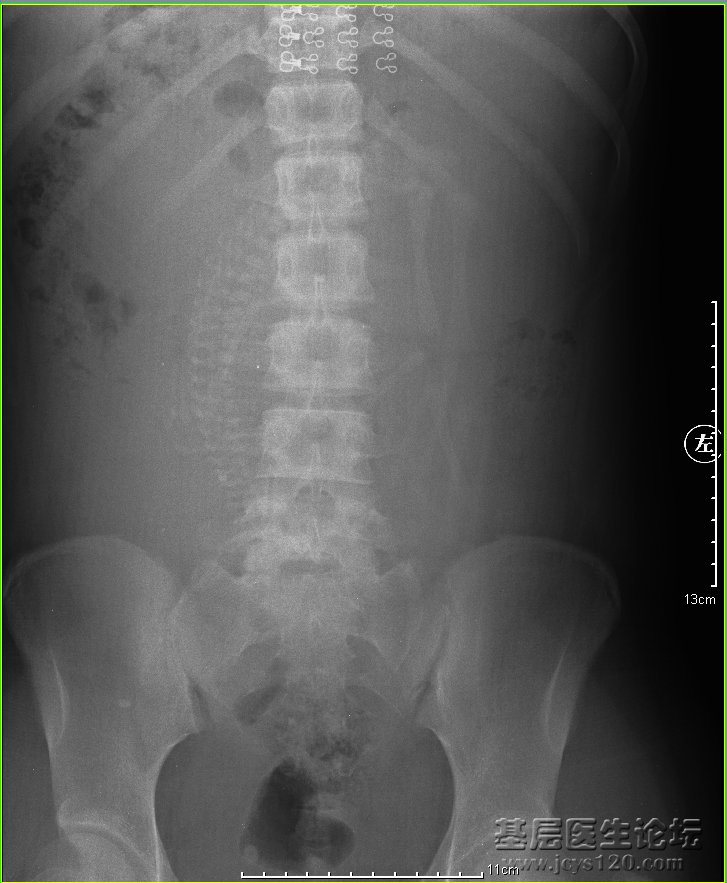

• 看看这个股骨头 attach_img agree  ...2

• 真人无奈 2013-7-2

• 女。26岁,有外伤史,5年前从楼梯上摔倒。现走路无跛行,下肢内收,外旋时轻度受限,无疼痛。大家看看,现在的病情状况,怎样治疗为妥。  阅读全文>